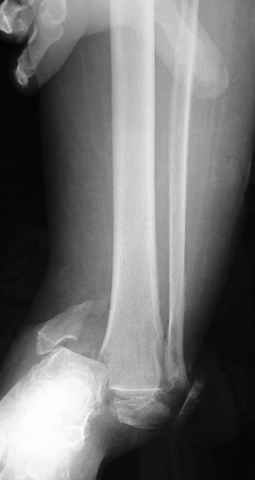

Pilon fracture:

-Появляется ориентир и остов, на чем можно строить восстановление, почему сперва малоберцовую, впервые обьяснили и описали (Pylon type and Ankle fractures) в середине 50х Rienau и Gay.

Восстановливая длину и ротацию малоберцовой кости, затем относительно легче произвести реставрацию остальных элементов перелома дистального эпиметафиза болшеберцовой кости.

где исследования на трупах показали, что малоберцовая кость участвует в стабильности голеностопного сустава, поддерживая наклон тарана (talar tilt) за счет связок. После ознакомления работой Ramsey в ортопедию ввели термин "при переломах голеностопного сустава смещенная

таранная кость следует за малоберцовой костью" т.е. связка не рвется, а тянет таран за собой, поэтому восстановление малоберцовой кости в

первую очередь, затем остальных элементов - стал классическим при лечении данной патолгии. Латеральная колонна (столб), дистальный

конец малоберцевой кости, к нему прикрепляется латеральный суставной фрагмент дистального эпиметафиза большеберцовой кости (как на снимке)

и таранная кость, которые при репозиции малоберцовой кости репонируются автоматически.